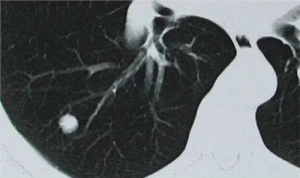

肺结节是指肺内单发或多发的直径不超过3cm的圆形或类似圆形的结节,影像学表现为密度增高的阴影。

注意:肿块﹥3cm;结节≤3 cm;小结节﹤2cm;微小结节﹤5mm。结节的大小与结节的良、恶性具有一定程度相关性,大于3cm的病灶多为恶性,而更微小的结节,良性的可能性居多。

1cm以下的结节不好判断,一定要找专科医生看。目前国内外对肺部结节都有指南,每过几年会根据实际情况更新,这是普通人所不能及时了解到的。根据日本体检指南,总而言之:圆形均匀钙化的结节,边缘清楚、光滑、密度均匀、长期观察无变化或缩小的结节是良性,0.5cm以下结节主要是密切观察。